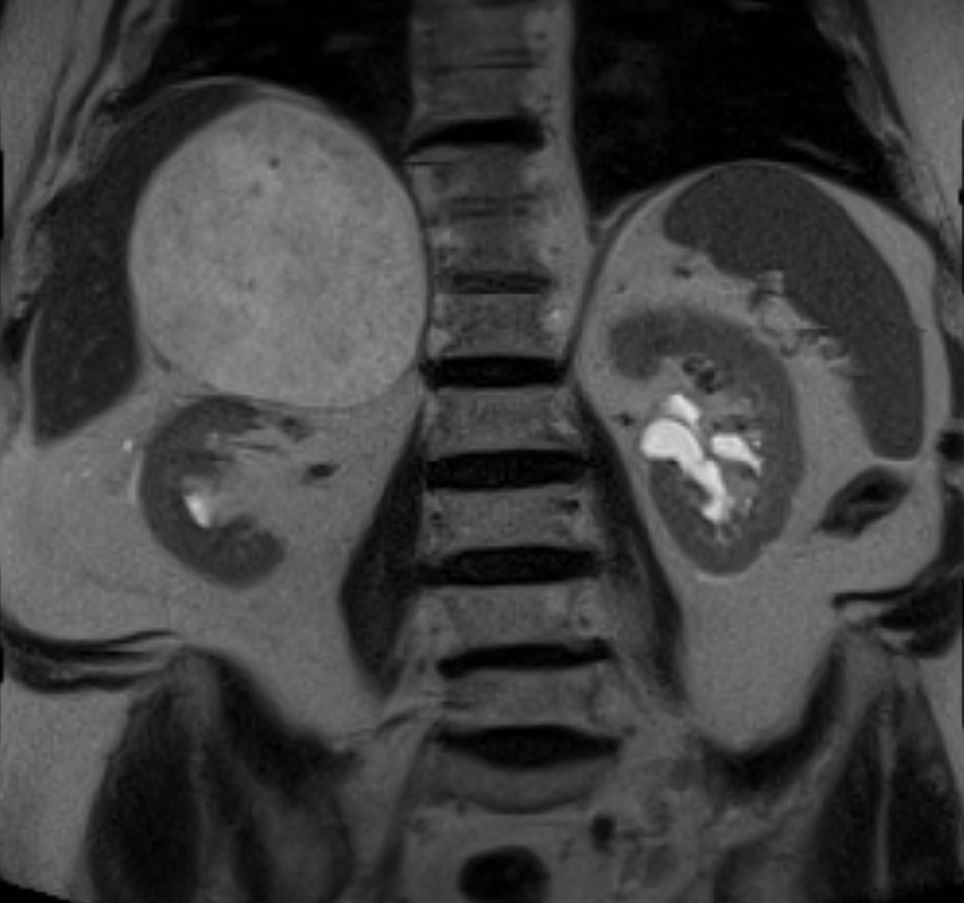

79-jähriger berenteter, adipöser Fleischer mit respiratorischer Insuffizienz. Urothel-Ca vor 15 Jahren. Jetzt kleines Bronchial-Karzinom. Beim Tumorstaging wurde ein großer NN-Tumor rechts entdeckt. | |||

![]() | |||